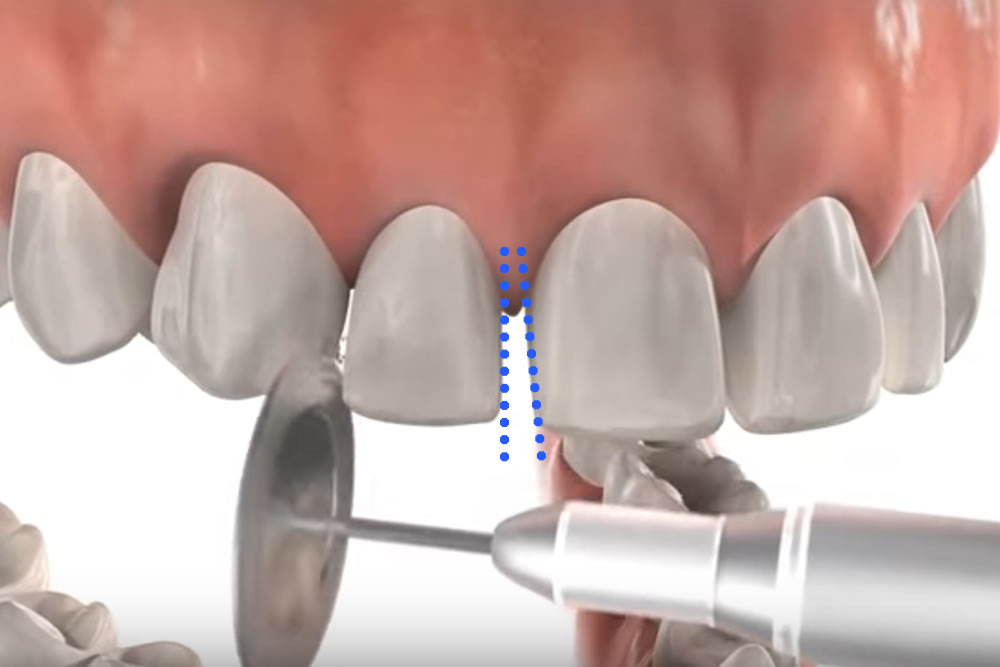

少し歯のエナメル質を削りスペースを生む

歯を抜歯せずに矯正に必要なスペースを確保する方法にディスキングと言う方法があります。歯の側面から健康被害が出ない程度にエナメル質を削り、歯が収まるスペースを作ります。歯のエナメル質は1~2㎜程度ありそのうちの約0.2~0.5㎜程削ります。